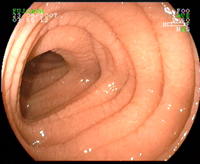

Duodénum normal